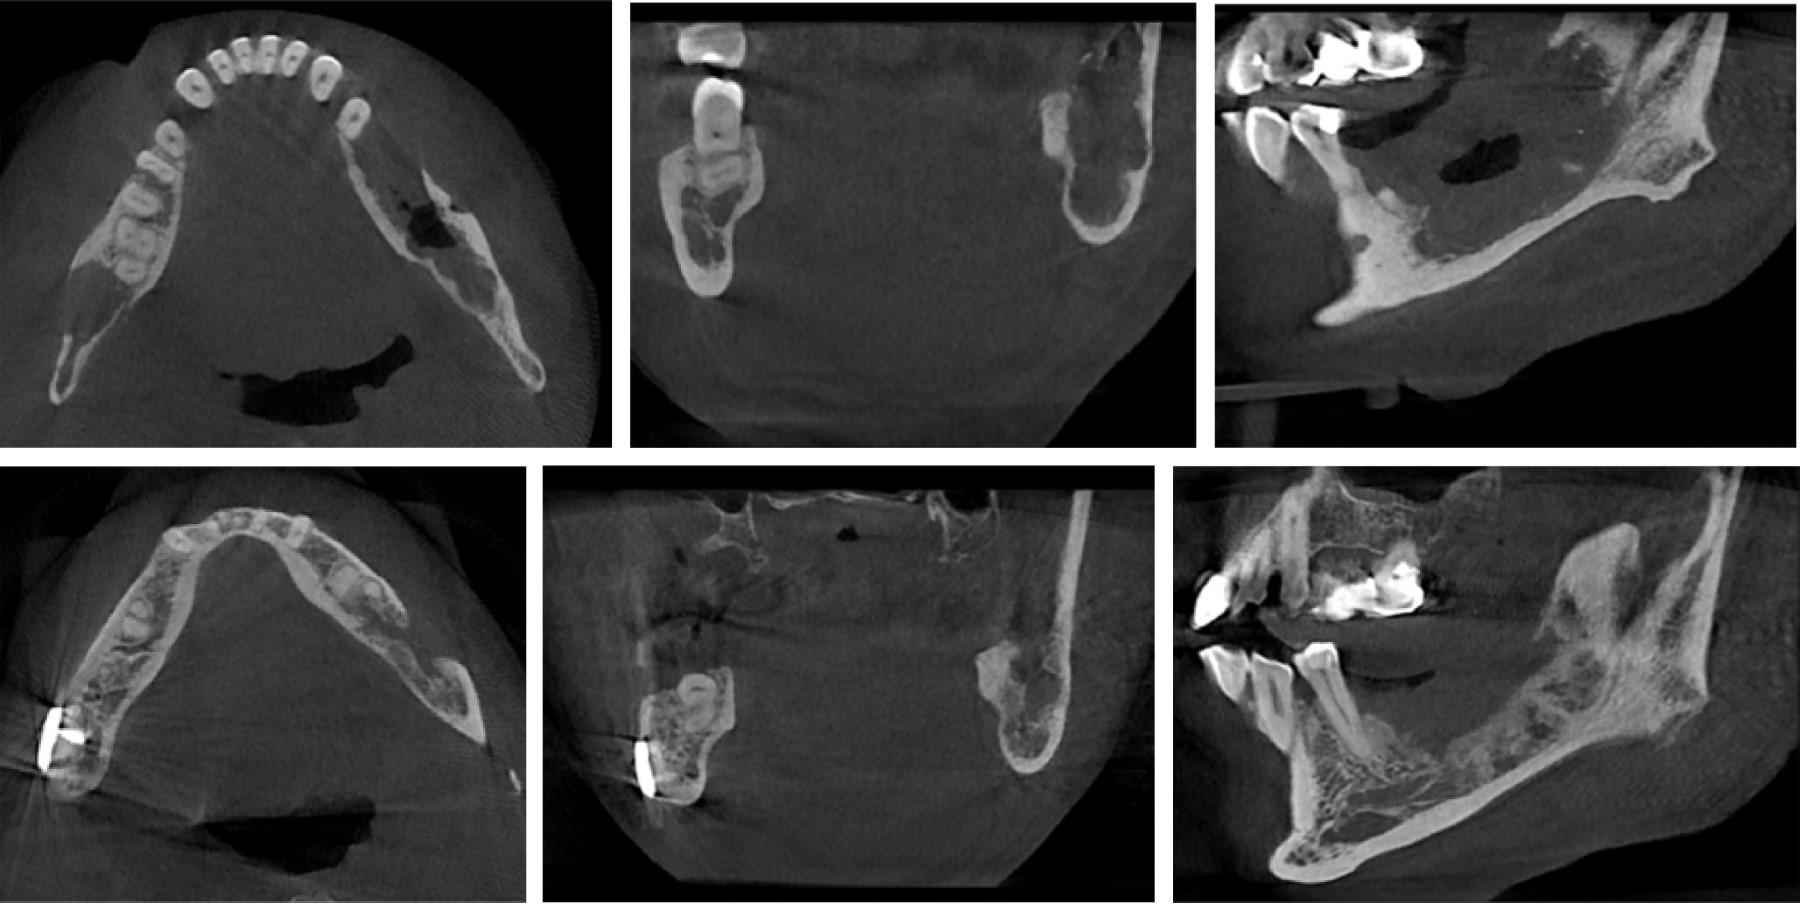

Se evalúa paciente en un postoperatorio tardío, con tomografía computarizada (Figura 6), donde se evidencia proceso de cicatrización adecuado, neoformación ósea en región de cuerpo y ángulo mandibular izquierdo. Al examen clínico: simetría facial relativa, apertura oral conservada, dentición permanente, edentulismo parcial mandibular, oclusión estable, cicatriz eutrófica en región de fondo de vestíbulo cuadrante III (Figura 7). Se indica control tomográfico a los 12 y 24 meses.

Figura 6